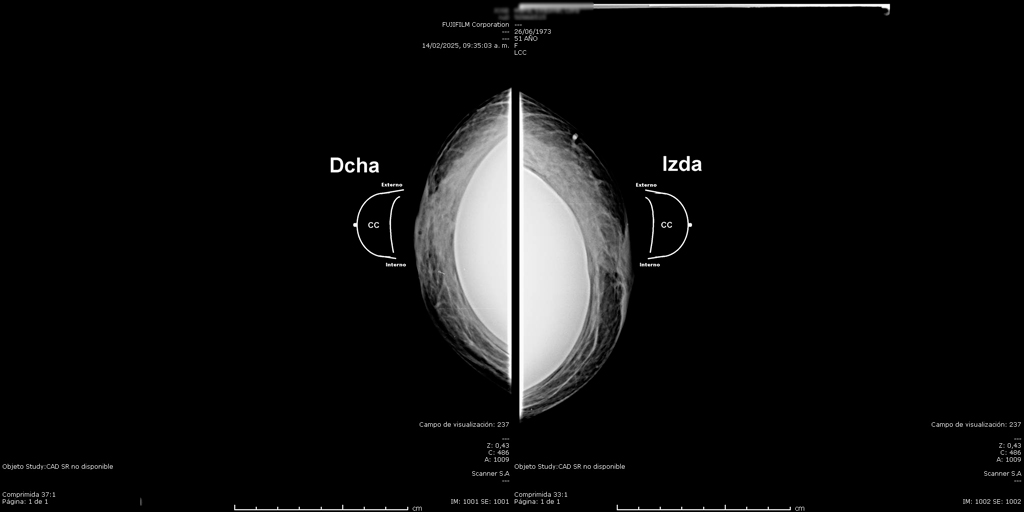

La mamografía es un estudio de diagnóstico por imagen que utiliza bajas dosis de rayos X para obtener imágenes detalladas del tejido mamario. Es una herramienta fundamental para la detección temprana del cáncer de mama y otras patologías mamarias, incluso antes de que sean evidentes al tacto o generen síntomas. Su uso regular en controles preventivos permite salvar vidas al facilitar diagnósticos oportunos y tratamientos más efectivos.

En SCANNER S.A, nuestros equipos digitalizados permiten detectar cambios mínimos en el tejido mamario con alta claridad, permitiendo asi tener un diagnostico preciso y entregar unos resultados reales a nuestros pacientes.